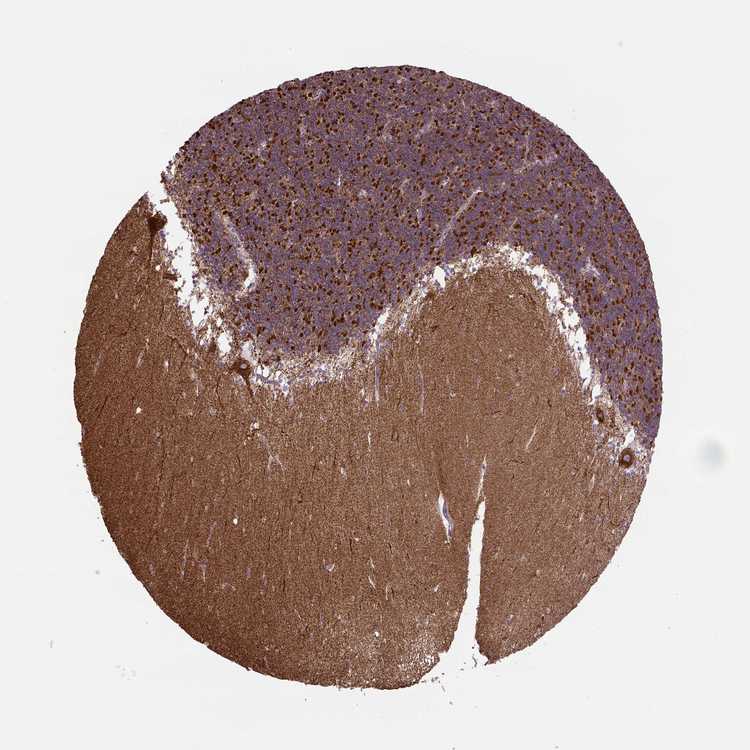

BRAIN CEREBELLUM Show tissue menu

CEREBELLUM - Expression summary

Cells in granular layer: High

Cells in molecular layer: Medium

Purkinje cells: High

CEREBELLUM - Antibody stainingi

Antibody staining in the annotated cell types in the current human tissue is reported as not detected, low, medium, or high, based on conventional immunohistochemistry profiling in selected tissues. This score is based on the combination of the staining intensity and fraction of stained cells.

Each image is clickable and will lead to virtual microscopy that enables deeper exploration of all samples and also displays staining intensity scores, fraction scores and subcellular localization as well as patient and tissue information for each sample.

Antibody HPA069328Antibody CAB016241

Purkinje cells HighHigh

Cells in granular layer HighHigh

Cells in molecular layer MediumHigh